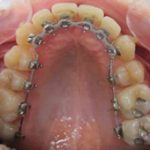

Arcade maxillaire avant traitement orthodontique, séquelles de maladie parodontale

Après traitement orthodontique et réalisation d’une attelle coulée collée (courtoisie Dr Patrick Fournier)